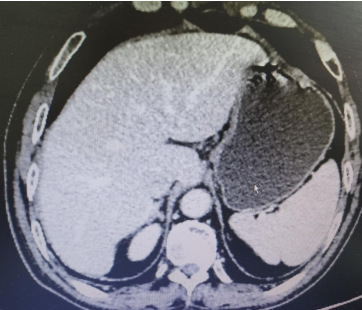

Abdominal CT films from March 3, 2020 (2 images)